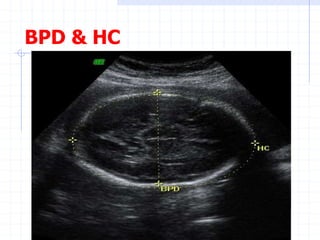

Biometry:

Biparietal diameter (BPD)

Head Circumference (HC)

BPD

BPD & HC